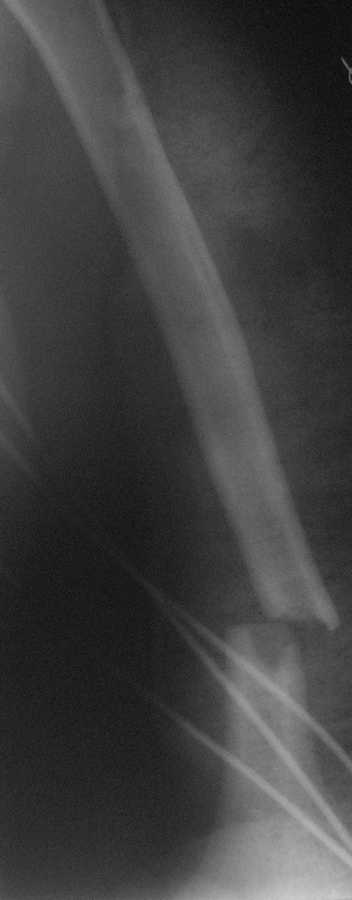

Перелом нестабильный, тактика - если позволяет сосояние больной, оперативное лечение. Как пример см. ниже, можно без скобы - стяжки с ЭПФ.

Представленный способ, функциональный, данная больная в качестве внешней иммобиллизации в течение 3-х недель полльзовалась косыночной повязкой, востановление функции плеча полное. Правда травма изолированная, но операция выполнялась через три недели после травмы, тот час после обращения ко мне - иногородняя.

Уважаемый товарисч.Данный перелом можно вылечить антероградным, ретроградным штифтованием, пластиной, аппаратом внешней фиксации, вытяжением за локтевой отросток на шине ЦИТО. Учитывая наличие тяжелой ЧМТ предпочтение должно отдаваться минимальноинвазивной технике.

Качество паредставленных Вами рентгеновских снимков крайне низкое, что косвенно свидетельствует об общей культуре работы в Вашем отделении.

Спасибо Алексей! Я и планировал провести антеградное штифтование но меня смущал относительно небольшой дистальный отломок. Может для кого-то данные вопросы и кажутся пустяком...но я только недавно начал использовать в своей работе штифты преимущественно Synthes. Еще раз спасибо

Всё правильно, просто я несколько разрозненно пытался сказать на частных примерах, то , что Вы систематизировали. Совершенно верно данный перелом можно и так и эдак, наиболее оптимально антеградное штифтование, хотя я бы предпочёл пластину LCP(просто - ну лучше у меня это получается и всё, а больному не вредит тот же функциональный способ). А низковато для неблокированного штифтования с конструкциями с термомеханической памятью, то, что представленно на втором снимке.